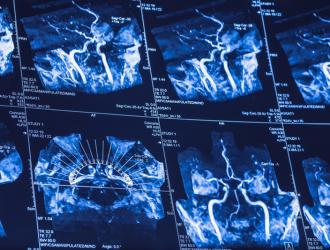

Uno studio internazionale su campioni di DNA appartenenti a oltre mezzo milione di individui provenienti da tutto il mondo ha identificato ventidue nuovi fattori di rischio genetici per l'ictus. Pubblicato su Nature Genetics, è il più grande studio genetico in materia.